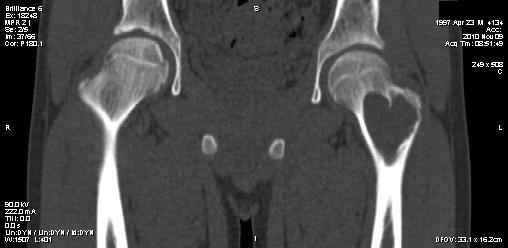

Сергей Тарасов 16 Ноябрь 2010, 15:09

Спасибо, коллеги, за комментарии!

Выполнили, что и запланировали. Обошлись одним крылом. Зафиксировали пластиной. Мысль о возможной фиксации TEN приходила, но... доступны только гвозди Эндера. А ими - не решились.